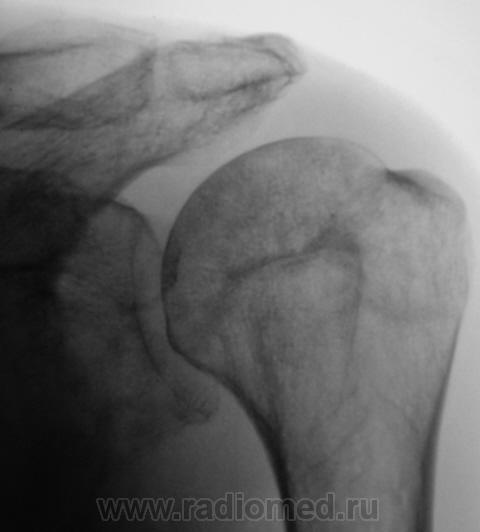

Валентин Львович, а с суставной впадиной лопатки все хорошо? У меня ее структура на подозрении...

Вы совершенно правы Татьяна Валентиновна. Я намеренно "обрезал" снимок, произведенный лаборантами, дабы акцентировать внимание на латеральном угле лопатки. Суставная поверхность лопатки и шейка внушают серьёзные подозрения, и с учетом "пороза" и структуры.

Снимок "без обрезания" - ниже. Врача-рентгенолога в кабинете не было, лаборанты, оценив его, начали "пытать" пациента. Оказалось, что флюорографию органов грудной полости, этот пациент, "проходил" лет 5 тому. Ну, и лаборанты приступили к стандартному исследованию органов грудной полости.